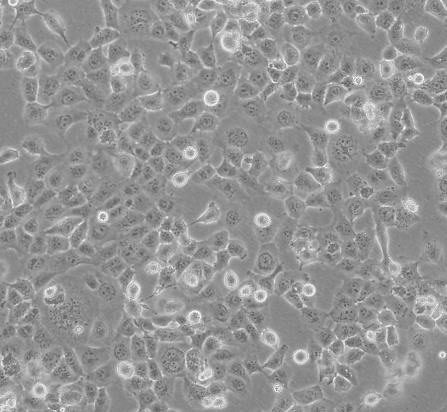

NCI-H69人小细胞肺癌贴壁细胞系源自一位54岁患有小细胞肺癌的白人男性,表达c-myb,v-fes,v-fms,c-raf1,Ha-ras,Ki-rasandN-rasmRNA。